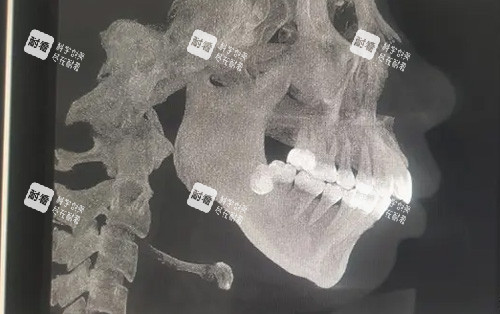

2. 齐全的术前检查

影像学检查:CT、X线片等。